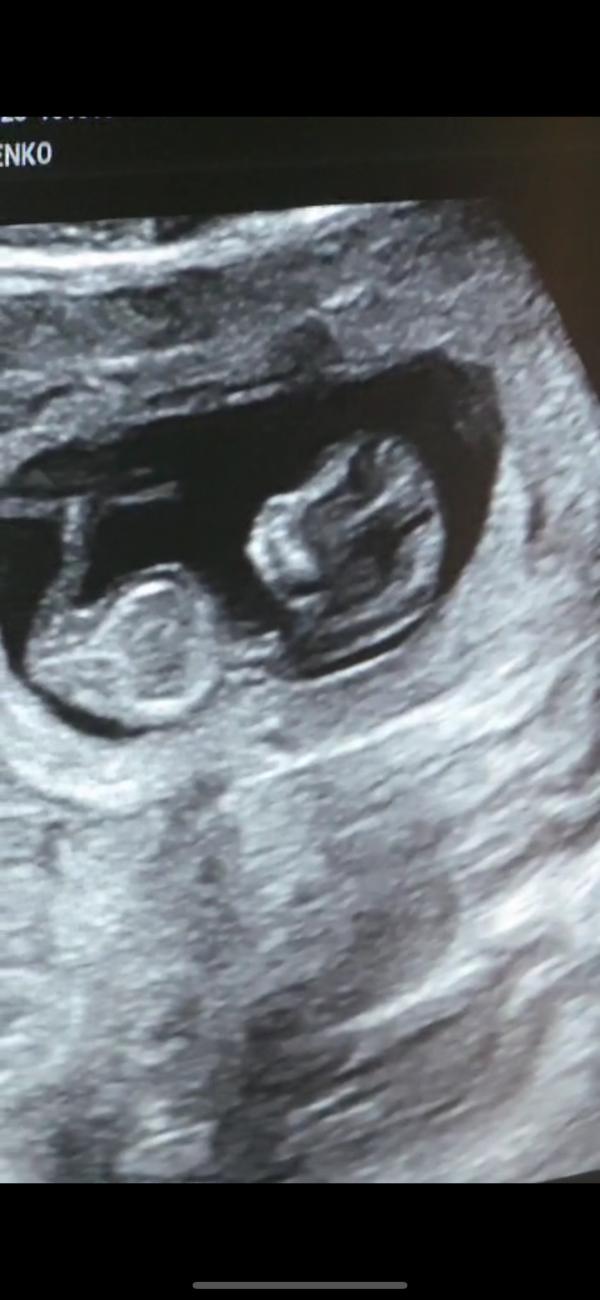

Живот сильно тянуло, поехали на узи внепланово.. по мес срок 11,4, по узи 11,5

В итоге сказали переносить на неделю раньше, тк ребенок уже большой, чтобы в сроки уложиться

Нашли ретрохориальную гематому,хотя я в прошлый раз не говорили о ней, но сказали что она не новая, и мол если будет мазать не пугайтесь..